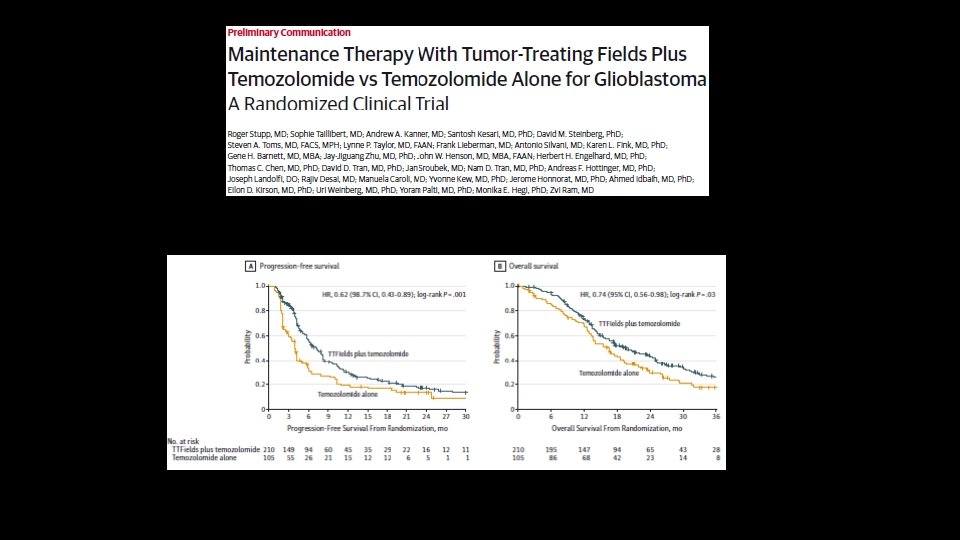

Glioblastoma Treatment • Gross Total Resection of Contrast-Enhancing area , if possible Stupp Regimen (External Limited Field Radiation and Concurrent Temozolomide followed by TMZ alone) • Gliadel, Avastin, Optune (TT Fields)- FDA approved